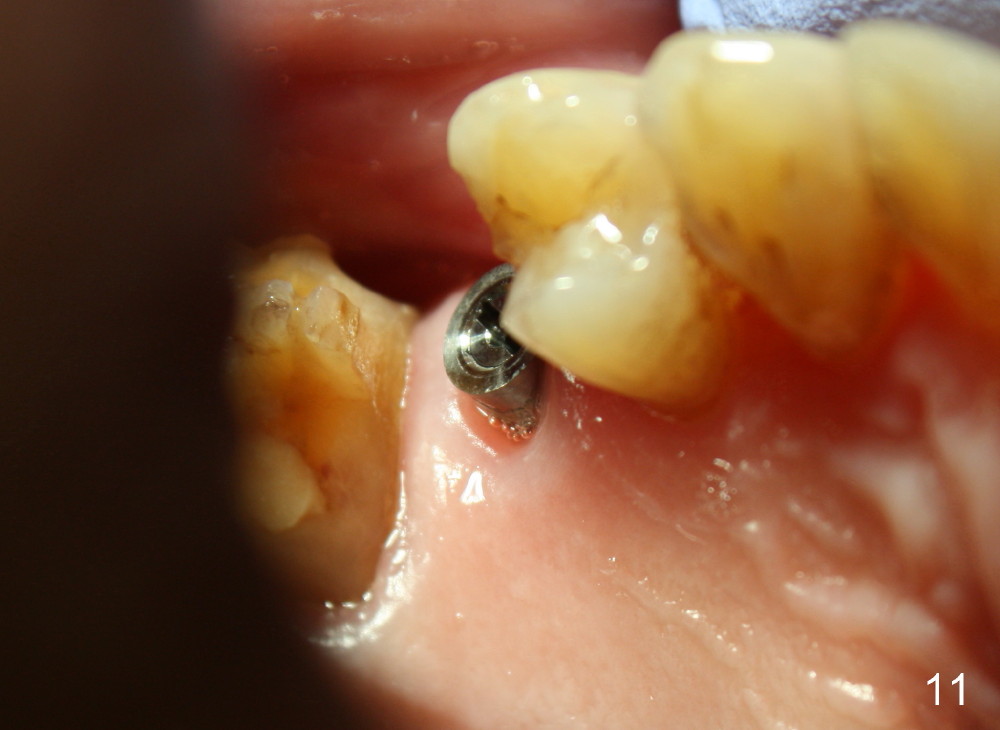

A 72-year-old man is a bruxer with #3 cusp fracture with chronic periapical radiolucency (Fig.1 *) and #4 acute crack.  It appears reasonable to take care of emergency (#4 extraction and immediate implant (Fig.3-7: 4.5x20 mm, 45 Ncm)) followed by root canal therapy or extraction for #3.  Eight (Fig.8) and 14 (Fig.9-11) days postop, the patient is doing fine and the wound heals normally.  But he does not agree any treatment for #3, since it is asymptomatic in spite of a fistula associated with the tooth (Fig.8,9 >).  Three months postop, the patient is still asymptomatic and is ready for #4 restoration since the tooth #28 cracks.  Follow-up PA shows the persistent distal gap (Fig.12 >, as compared to Fig.4), accompanied with crestal bone resorption (*).  Clinically the implant has mild mobility and light tenderness. The patient still refuses #3 treatment. It appears that the implant has failed to osteointegrate.  In brief, do not place an immediate implant next to active infection.